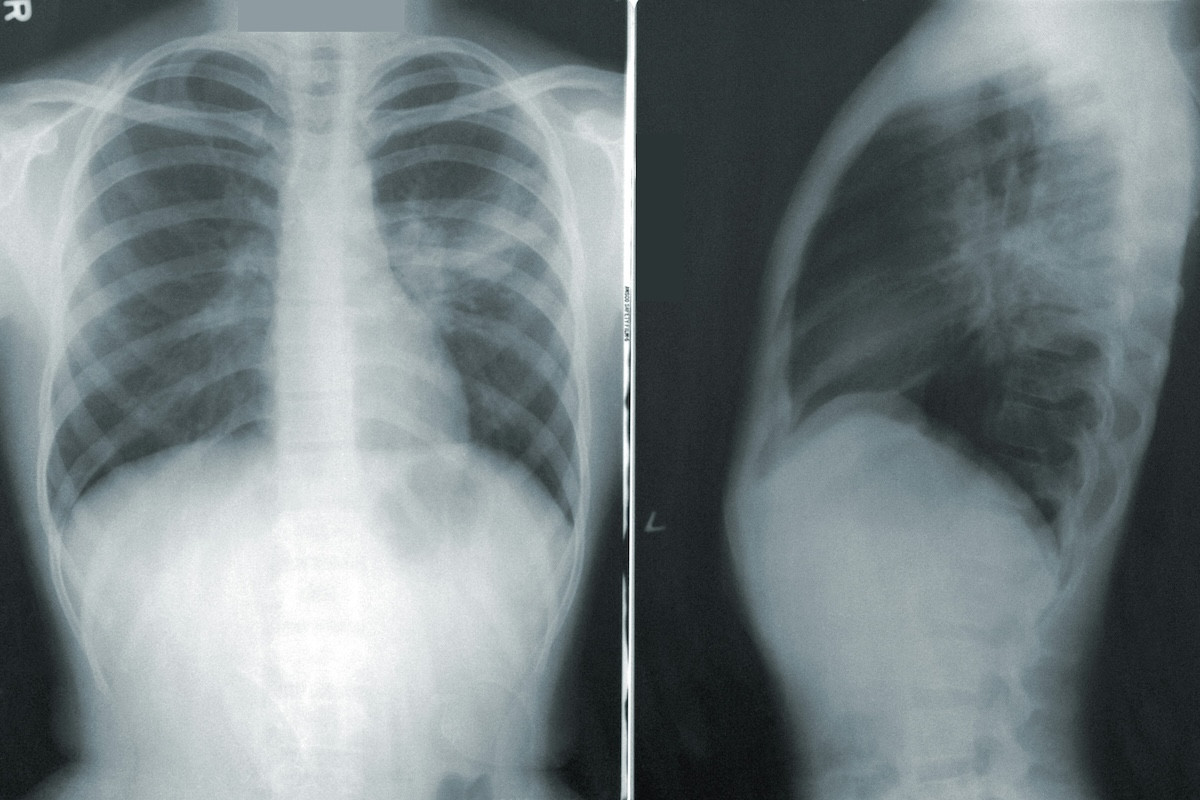

Οι περισσότερες περιπτώσεις καρκίνου του πνεύμονα έχουν ως κοινή αιτία το κάπνισμα. Ωστόσο, δεν είναι η μοναδική.

Το ραδόνιο, ένα άχρωμο και άοσμο αέριο, είναι η δεύτερη κύρια αιτία καρκίνου του πνεύμονα μετά από το κάπνισμα.